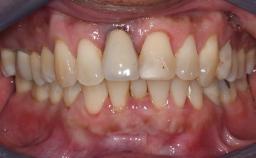

The patient presented with a failing tooth-supported fixed dental prosthesis with cantilever extension replacing the right maxillary central incisor. His chief presenting complaint was poor esthetics, in particular the dark discolored margin around the abutment tooth, the maxillary left central incisor. He reported a history of trauma at a young age, which necessitated the replacement of his maxillary right central incisor as well as root canal therapy of the adjacent left central incisor. The existing prosthesis had been in situ for over 20 years. The initial periapical radiograph displayed good proximal bone levels at the adjacent teeth and a wide incisive canal, which was a concern. The left central incisor presented a very wide root canal treatment with compromised radicular dentin thickness, which was a consideration in the decision between a new tooth-supported fixed dental prosthesis vs. an implant-supported prosthesis. After a lengthy discussion on the risks and benefits of both treatment options, the patient decided on a single-tooth implant replacement.

Prosthesis Type FDP

Esthetic Risk High